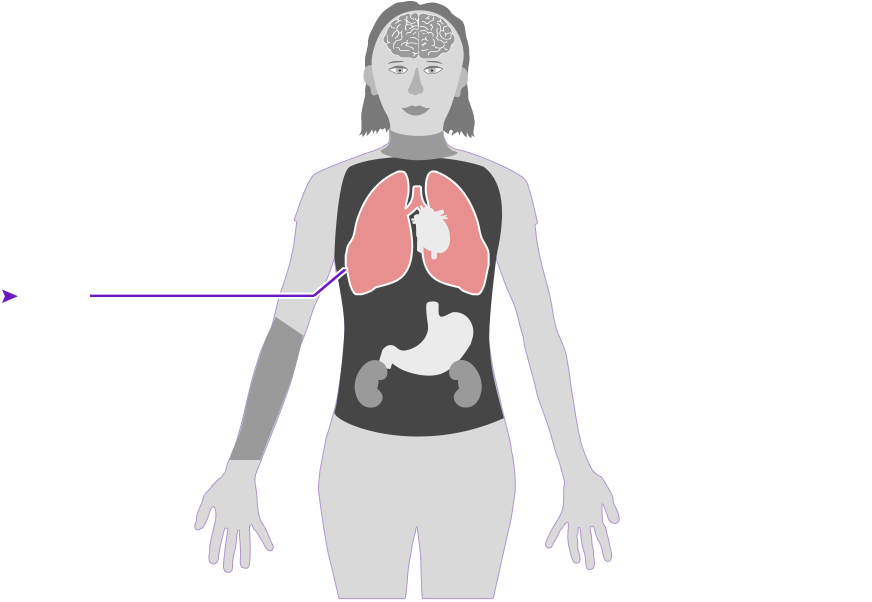

Check out how mercury can affect the human body. Click on the different parts of the body to see what can happen when people are poisoned by mercury. How serious these health effects are may vary depending on how much mercury gets into your body — and how long you breathe it in.

Health effect caused by breathing in high levels of mercury vapors (fumes) over a short period of time

Health effect caused by breathing in high levels of mercury vapors (fumes) over a short period of time  Health effect caused by breathing in lower levels of mercury vapors over a long period of time

Health effect caused by breathing in lower levels of mercury vapors over a long period of time